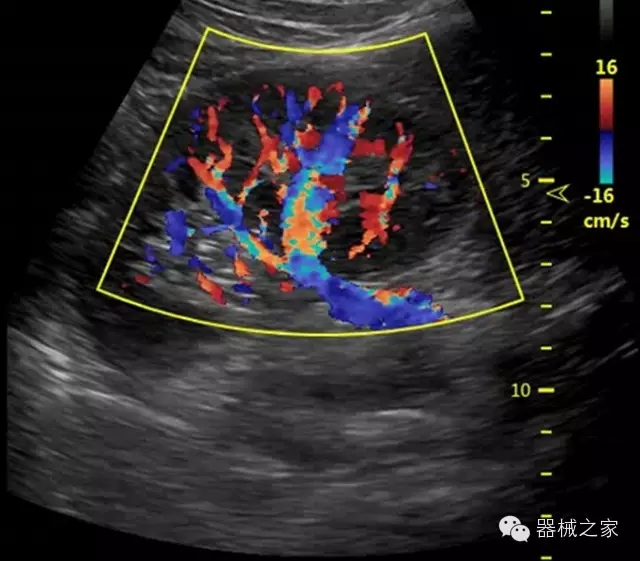

臨床圖片賞析

·全球目前唯一一款配備主機雙探頭接口,整機重量(含電池)在5公斤以內(nèi)的便攜式彩超;

·獨有的HoloTM PW 實時3取樣門PW成像技術,精確進行血管診斷;

·一鍵優(yōu)化B、Color、PW,Auto Doppler自動識別血管位置、偏轉角度等,提高工作效率;

·30°超廣角精細偏轉成像技術,更優(yōu)異的頻譜圖像;